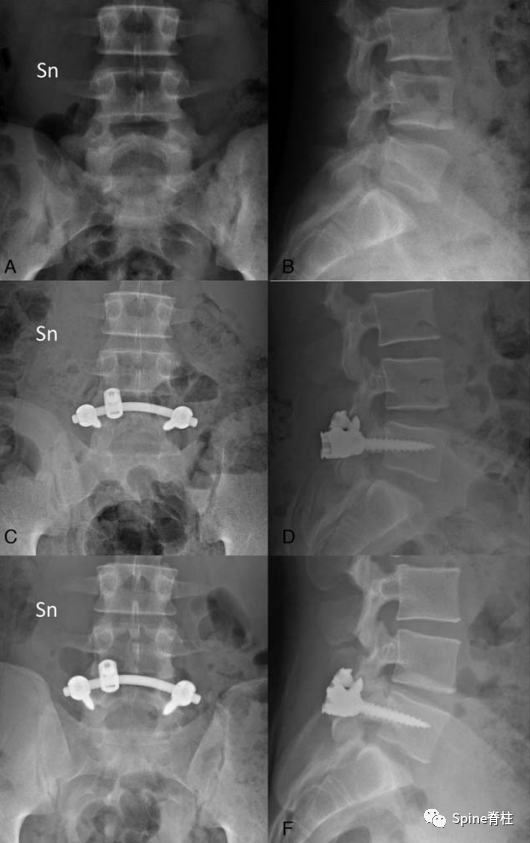

2019年国内解放军总医院第七医学中心李放教授团队。根据临床特点和影像学表现将所有病例分为3型:

• A型为单纯型峡部裂,无椎间盘突出及腰椎滑脱;

• B型为峡部裂伴有轻度椎间盘突出或I度滑脱,无神经压迫症状及体征;

• C型为峡部裂合并I度或Ⅱ度滑脱并椎间盘突出同时有神经压迫症状及体征。

并建议保守治疗无效的青年战士A、B型腰椎峡部裂病例采用椎弓根螺钉固定,峡部自体髂骨原位植骨融合率高,效果好,C型战士峡部裂则宜采用后路椎间植骨融合椎弓根螺钉内固定术。